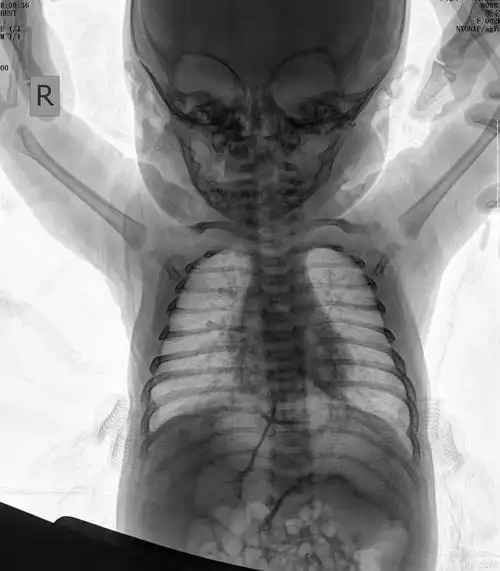

中医院放射科带您解读小儿肺炎

宝宝一岁支气管肺炎

问:宝宝初步被诊断为支气管肺炎,平时精神很好,也能吃饭,就是总在后

儿童胸片 大家帮忙分析一下!